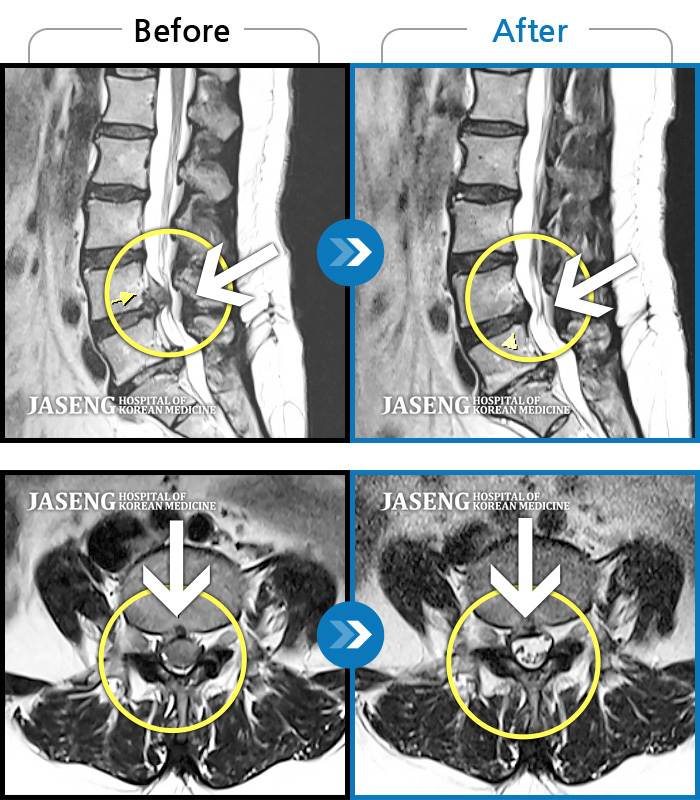

Before

After

환자에게 사전 동의를 받아 동일 조건에서 촬영되었습니다.

개인에 따라 치료 후 부작용이 발생할 수 있으니 의료진과 상담 후 치료를 진행하시기 바랍니다.

허리통증, 왼쪽 다리 저림 및 통증

허리 좌측에서 종아리 후면까지 통증, 묵직한 증상